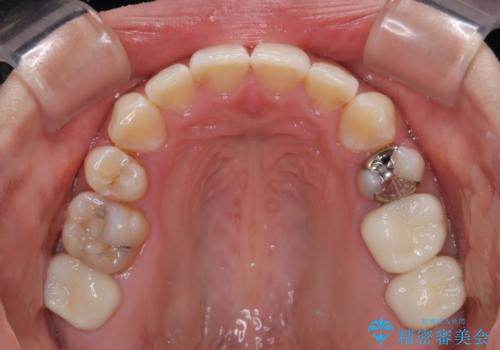

第二小臼歯抜歯はイレギュラーな治療手段であり、治療期間が延びる傾向にありますが、予定よりも早い2年間で終えることができました。

奥歯の虫歯は事前に矯正治療用の仮歯に置き換えて矯正治療を行い、装置除去後にセラミッククラウンにて補綴治療を行うこととしました。